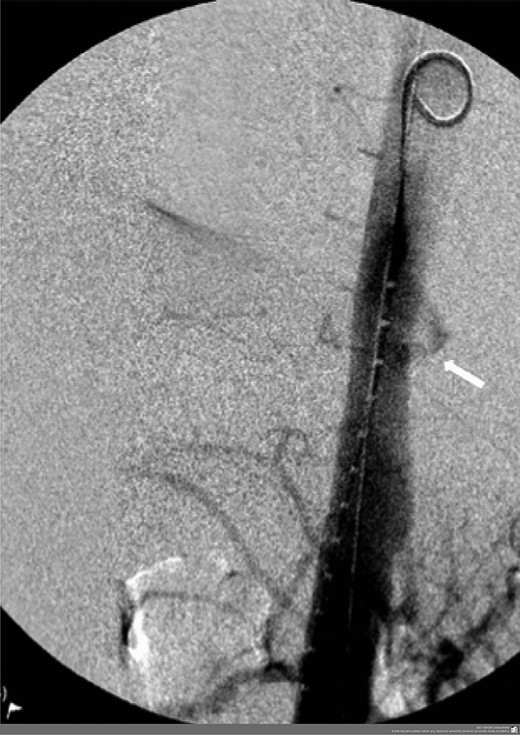

A 57-year-old male presented haemodynamically unstable with a blood pressure of 85/50 mmHg and a heart rate of 136 bpm with haematemesis, melaena and 4-day history of back pain. Fifteen years previously he was treated for a poorly differentiated adenocarcinoma (pT3 pN1 MX) close to the gastro-oesophageal junction with chemotherapy and trans-hiatal oesophagectomy. He received no radiotherapy. Apart from being a life-long smoker he had no other positive social risk factors or medical history. He underwent immediate oesophago-gastro-duodenoscopy (OGD). This showed fresh and clotted blood in the gastric remnant but no bleeding source was identified. He had a pulseless arrest during the OGD but underwent successful cardiopulmonary resuscitation. Following this a CT angiogram was performed. This demonstrated a fistula between the neo-oesphagus and the thoracic aorta (Fig. 1). Following discussion between an upper gastro-intestinal surgeon, a vascular surgeon and an interventional radiologist the patient was taken to the operating theatre. Under general anaesthesia an initial thoracic aortogram was performed from the right groin to confirm the presence and location of the AGF (Fig. 2). Following this, a covered thoracic stent graft (Cook Medical ZTA-24-105/diameter of 24 mm and length of 105 mm), was inserted via the femoral artery under image guidance. The stent graft, usually used in aneurysmal repair, was placed in the thoracic aorta across the fistula and occluded it. Subsequent angiogram showed no leak (Fig. 3). The patient became haemodynamically stable and had an uneventful recovery.

Angiogram prior to primary aortic stenting; leak via fistula demonstrated by arrow.